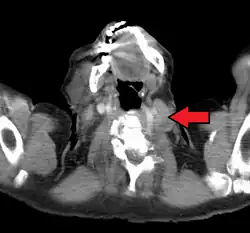

An enlarged Virchow's node as seen on CT

Malignancies of the internal organs can reach an advanced stage before giving symptoms. Stomach cancer, for example, can remain asymptomatic while metastasizing. One of the first visible spots where these tumors metastasize is one of the left supraclavicular lymph node.